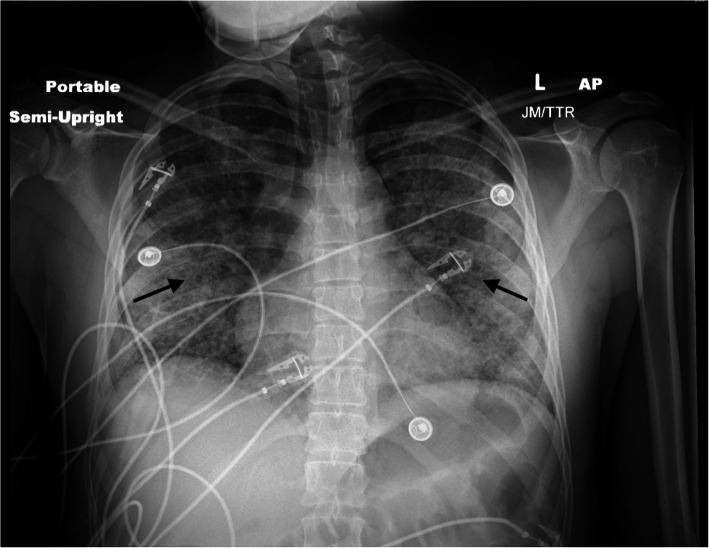

Laboratory studies revealed leukocytosis of 17.0 × 109/L with 93% neutrophils and an elevated lactic acid of 1.9 mmol/L. The findings of the patient’s chemistry panel were unremarkable. His urine drug screen result was positive for cannabinoids and benzodiazepines. His erythrocyte sedimentation rate was slightly elevated at 63 mm/hour. His human immunodeficiency virus and hepatitis B and C virus test results were negative. A viral panel was obtained, which showed positive results for rhinovirus and enterovirus, but otherwise negative findings were reported. This patient’s hospitalization occurred before the coronavirus disease 2019 (COVID-19) pandemic; therefore, no COVID-19 testing was available at the time. He had negative test results for antineutrophil antibodies, cytoplasmic and perinuclear antineutrophil cytoplasmic antibodies, and myeloperoxidase. His echocardiogram demonstrated a left ventricular ejection fraction of 64%; otherwise, he had no effusion, no vegetation, or other acute findings. A plain chest x-ray (CXR) (Fig. 2) demonstrated diffuse central predominant interstitial opacities. A computed tomographic (CT) angiogram of the chest was then obtained (Figs. 3 and 4), which confirmed diffuse bilateral interstitial infiltrates, with no evidence of vascular injury or pulmonary embolism.